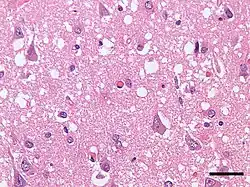

| Micrograph showing spongiform degeneration (vacuoles that appear as holes in tissue sections) in the cerebral cortex of a patient who had died of Creutzfeldt–Jakob disease. H&E stain, scale bar = 30 microns (0.03 mm). | |

Prion diseases are marked by mental and physical deterioration that worsens over time.[5][6] A defining pathologic characteristic of prion diseases is the appearance of small vacuoles in various parts of the central nervous system that create a sponge-like appearance when brain tissue obtained at autopsy is examined under a microscope.[2][3] Other changes in affected regions include the buildup of PrPSc, gliosis, and the loss of neurons.[7]

The degenerative tissue damage caused by prion disease in the nervous system is characterised by four features: spongiform change (the presence of many small vacuoles); the death of neurons; astrocytosis (abnormal increase in the number of astrocytes); and deposits of abnormal PrP (some of which have the characteristics of amyloid).[26] These neuropathological features have formed the basis of the histological diagnosis of prion diseases for many years, although it has been recognized that these changes are highly variable both from case to case and within the central nervous system in individual cases.[27][26] In humans, prion diseases with different genetic or infectious causes often have different patterns of pathology. For instance, amyloid plaques are rare in most prion diseases, but they are common in some diseases such as kuru and variant CJD. Owing to the rarity of amyloid per se in prion diseases, it is thought that non-amyloid forms of PrPSc are responsible for neurodegeneration.[26] In rare instances of human prion disease, tauopathy resembling the neurofibrillary tangles in Alzheimer's disease is present, highlighting the many ways in which the pathology of prion diseases can vary.[26] Despite this variation, all prion diseases have in common the buildup of abnormal PrP in the nervous system.

Discovery of spongiform change in scrapie. Another key event in the history of transmissible spongiform encephalopathies was the discovery of spongiform change (vacuolation) in the nervous system of sheep by Charles Besnoit and colleagues in the late 1890s.[35][34] Prior investigations had failed to identify pathologic features that were linked to the disease.[71] The realization that vacuolation is a characteristic of scrapie was a critical step toward the pathological definition of the transmissible spongiform encephalopathies in general.[72]